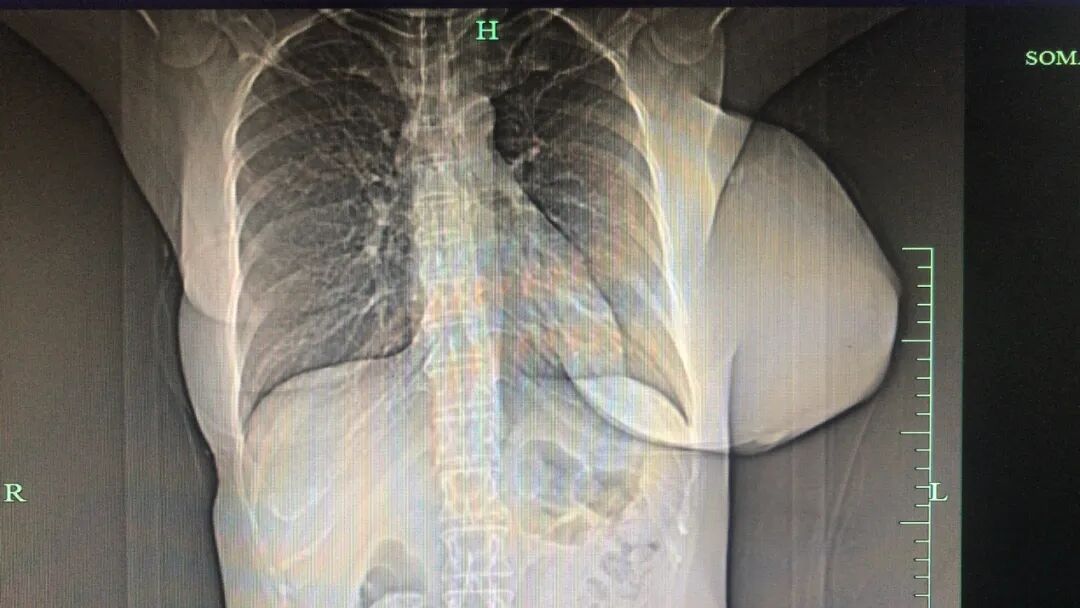

王女士影像检查结果 医院供图

前段时间,王女士托着胸走进了浙大四院乳腺外科专家门诊。浙大四院乳腺外科学科带头人、浙大二院乳腺科主任陈益定主任医师检查发现,病患部位触目惊心,左侧乳腺肿瘤罕见巨大,状如西瓜样,皮肤表面灰红可见糜烂。

陈主任表示,如果病情继续发展,患者乳房皮肤会承受不住增大的肿瘤细胞而破烂,另一方面还可能出现肿瘤细胞扩散、转移到肺部,拖延越久获得痊愈的希望就越渺茫。

术前,浙大四院乳腺外科团队开展复杂病例讨论,制定详细手术方案,这是一项风险极大要求极高的艰巨任务。手术由陈益定主任主刀,行全麻下单乳切除。术中发现,肿瘤已经浸润到乳腺后方的肌肉组织,再晚一些切除,手术的创面可能更大,甚至会失去手术的机会。

经过紧张的手术,乳腺外科专家们默契配合,仔细分离肿瘤以及周围正常组织,游离皮瓣,顺利将肿瘤以及侵犯的肌肉组织切除,并且修复缺损,用最小的创伤,解除了患者的巨大肿瘤负荷。切除的巨大肿瘤标本足有6斤重,大小28*16*16cm,病理报告显示是恶性叶状肿瘤。